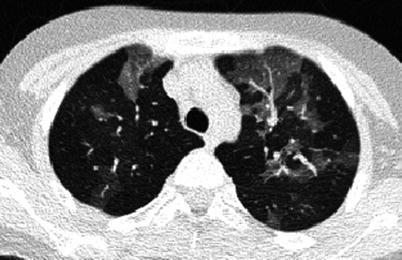

Children represent 2 % of the reported cases of human immunodeficiency virus (HIV) infection. Most children are infected after vertical transmission from their mother, and majority develop acquired immunodeficiency syndrome (AIDS) early in life. There is increased susceptibility to bacterial, viral, fungal, protozoal, and opportunistic infections. Lobar or segmental consolidations are the most common patterns (Marks et al. 1996). Mycobacterial infection can be seen in AIDS patients, and the radiographic appearance mimics that seen in immunocompetent children with primary tuberculosis. Mycobacterium avium-intracellulare is also encountered later in the course of disease and imaging findings cannot be distinguished with other forms of mycobacterial infections (Collingsworth 2005). Pneumocystis jiroveci is the most common opportunistic pulmonary infection in children with AIDS, occurring in up to 50 %, and is the leading pulmonary cause of death (Jeanes and Owens 2002). Radiographic appearances are variable and include hyperinflation with diffuse bilateral interstitial or nodular infiltrates from the perihilar region to the periphery, which often progresses to widespread alveolar opacities with air bronchogram (Fig. 13.30). Cavitary nodules and cysts can be seen, with pneumothorax and/or pneumomediastinum as common complications. HRCT findings include patchy or diffuse ground-glass opacity, consolidation, cyst or cavities, centrilobular opacities, nodules, peribronchial cuffing, and interlobular septal thickening (Jeanes and Owens 2002; Collingsworth 2005).

Fig. 13.30.

Pneumocystis jiroveci infection. Radiograph of a 10-month-old boy diagnosed with severe combined immune deficiency syndrome showing diffuse reticulonodular interstitial pattern in both lungs with development of lung consolidations (a). Radiograph of a 14-month-old girl with HIV infection showing diffuse, bilateral interstitial lung pattern extending from the hilum (b). There is a cyst noted on the peripheral right lung (arrow)